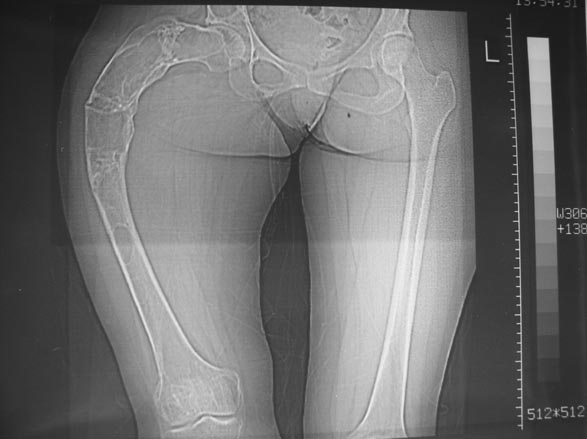

Женщина 28 лет, Больна с 12 летнего возраста, Когда после адекватной травмы получила перелом бедра. На рентгенограммах выявлено какое-то (рентгенограмм и документов нет) изменение бедренной кости, была оперирована, имеется гистологическое заключение - фиброзная дисплазия.дСформировалась деформация бедра. На сегодня - Укорочение 7см. Грубая деформация бедра по типу "пастушьей палки", последний патологический перелом в январе 2004г., консолидировавшийся при консервативном лечении. Имеются грубые изменения и в надвертлужном массиве.-- С уважением, Leonid

Мне 15 лет. Случилось все когда мне было 10 лет 26.12.04 я был дзю-доистом и в одном из соревнований сломалась правая бедренная кость. перелом был внутренний со смещением. Взяли и сделали операцию, поставили пластинку и тем самым заложили инфекцию. Потом кость начала гнить и сняв пластинку, через три месяца поставили аппарат Илизарова. Он отлежал месяцев шесть с мая по сентябрь. и когда снимали кость снова отошла. то есть сломалась. по правую сторону бедра были дырки из которых шел гной и которые закрылись уже в 2006 году. далее поправив поставили в гипс который остался больше шести месяцев. прошли месяцы и все вроде было в порядке. потом опять сломалась изза простейшей причины в августе 2006 года. опять поставили в гипс. прошло время и снова когда спускался с бордюра сломалась в четвертый на данный момент последний раз 23 мая 2008 года. с тех пор кроме патологических разломов кости тревожила еще одна проблема. та самая деформация. только со временем она становиться еще сильней.